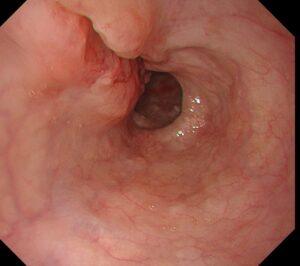

1ヶ月前から便秘と下痢を繰り返し出現した進行大腸癌の一例

2026-03-08